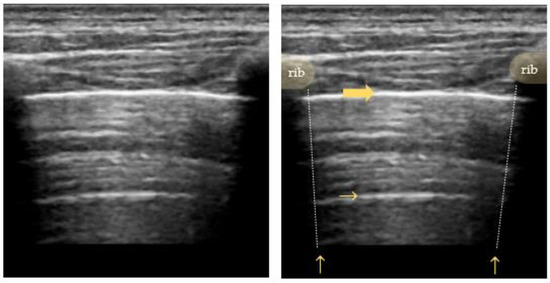

4.2. Interstitial Syndrome

- Lichtenstein, D.; Mézière, G.; Biderman, P.; Gepner, A.; Barré, O. The Comet-Tail Artifact. An Ultrasound Sign of Alveolar-Interstitial Syndrome. Am. J. Respir. Crit. Care Med. 1997, 156, 1640–1646. [Google Scholar] [CrossRef]

- Volpicelli, G.; Elbarbary, M.; Blaivas, M.; Lichtenstein, D.A.; Mathis, G.; Kirkpatrick, A.W.; Melniker, L.; Gargani, L.; Noble, V.E.; Via, G.; et al. International Evidence-Based Recommendations for Point-of-Care Lung Ultrasound. Intensive Care Med. 2012, 38, 577–591. [Google Scholar] [CrossRef] [PubMed]

- Volpicelli, G.; Gargani, L. Interstitial Syndrome. In Chest Sonography, 4th ed.; Springer: Cham, switzerland, 2017; pp. 45–50. [Google Scholar] [CrossRef]

- Liteplo, A.S.; Marill, K.A.; Villen, T.; Miller, R.M.; Murray, A.F.; Croft, P.E.; Capp, R.; Noble, V.E. Emergency Thoracic Ultrasound in the Differentiation of the Etiology of Shortness of Breath (ETUDES): Sonographic B-Lines and N-Terminal pro-Brain-Type Natriuretic Peptide in Diagnosing Congestive Heart Failure. Acad. Emerg. Med. 2009, 16, 201–210. [Google Scholar] [CrossRef]

- Bedetti, G.; Gargani, L.; Corbisiero, A.; Frassi, F.; Poggianti, E.; Mottola, G. Evaluation of Ultrasound Lung Comets by Hand-Held Echocardiography. Cardiovasc. Ultrasound 2006, 4, 34. [Google Scholar] [CrossRef]

- Lichtenstein, D.A.; Mezière, G.A.; Lagoueyte, J.F.; Biderman, P.; Goldstein, I.; Gepner, A. A-Lines and B-Lines: Lung Ultrasound as a Bedside Tool for Predicting Pulmonary Artery Occlusion Pressure in the Critically Ill. Chest 2009, 136, 1014–1020. [Google Scholar] [CrossRef]

- Copetti, R.; Soldati, G.; Copetti, P. Chest Sonography: A Useful Tool to Differentiate Acute Cardiogenic Pulmonary Edema from Acute Respiratory Distress Syndrome. Cardiovasc. Ultrasound 2008, 6, 16. [Google Scholar] [CrossRef]

- Lichtenstein, D.; Mezière, G. A Lung Ultrasound Sign Allowing Bedside Distinction between Pulmonary Edema and COPD: The Comet-Tail Artifact. Intensive Care Med. 1998, 24, 1331–1334. [Google Scholar] [CrossRef]